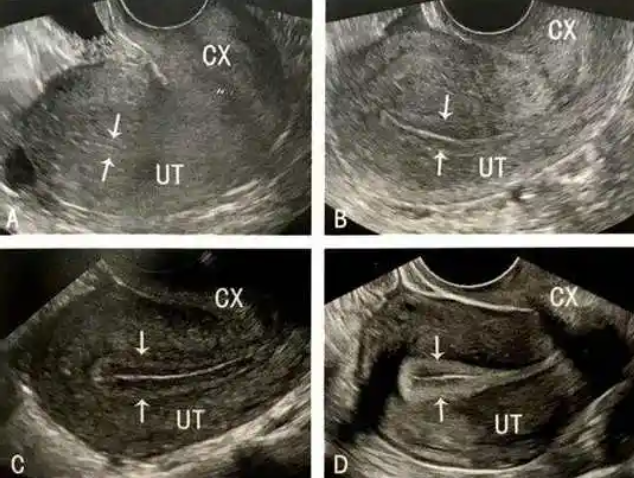

在试管婴儿周期中,部分患者会遭遇“反复种植失败”——即多次移植优质胚胎均未成功。一个关键原因在于,目前临床评估子宫内膜容受性(接纳胚胎的能力)的方法,如超声测量内膜厚度或检测少数生物标志物,提供的信息较为有限,难以全面、动态地反映每位患者独特的子宫内环境,导致在临床上有时依赖于经验判断[1]。

本研究主要突破是创建了源自患者自身细胞的三维血管化子宫内膜芯片。该芯片不仅在结构上复刻了真实子宫内膜的多层组织,更能动态模拟月经周期中为胚胎着床做准备的生理变化,包括关键的血管生成过程。这相当于为每位患者制作了一个可在实验室中进行深入、动态研究的“微型子宫内膜”,为个体化研究奠定了坚实基础。

基于上述高度仿真的模型,研究团队开发了一套名为ERS2的子宫内膜容受性评分系统。该系统通过量化分析芯片中与胚胎着床密切相关的特定分子表达水平及血管生成状态,进行综合评分。初步验证显示,该评分与患者后续的实际妊娠结局具有高度相关性,未来有望成为一种更客观、更精准的评估工具。